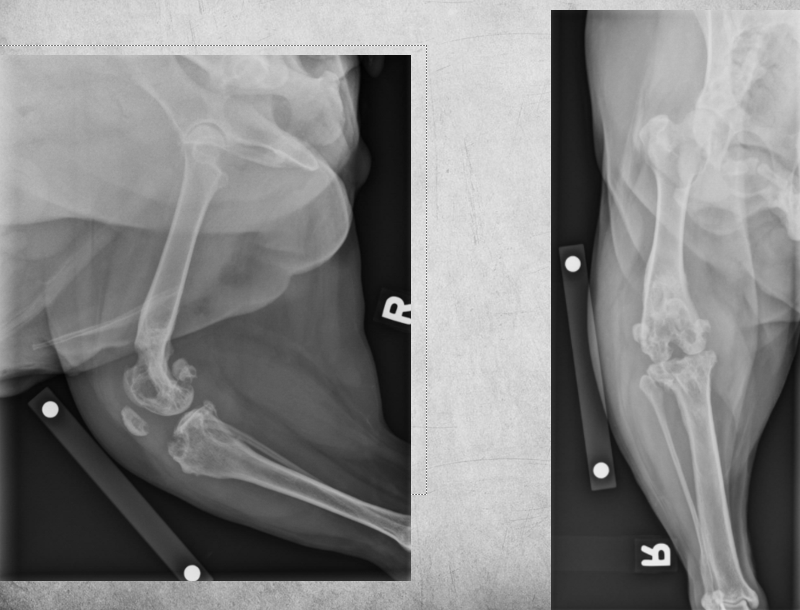

10

2 years old male castrated cat

Severe sudden onset lameness of pelvic limb

A

Displaced capital physeal fracture of the left femoral head with mild cranial displacement of the femoral neck. On the frog-legged VD projections, this displacement is not visualizing so well.

Most of the physes of the pelvic limbs are at least partially open, including the intact right femoral capital physis (castrated young).

Diagnosis: Left sided capital physeal fracture of the left pelvic limb and delayed physeal closure in both hind limbs.